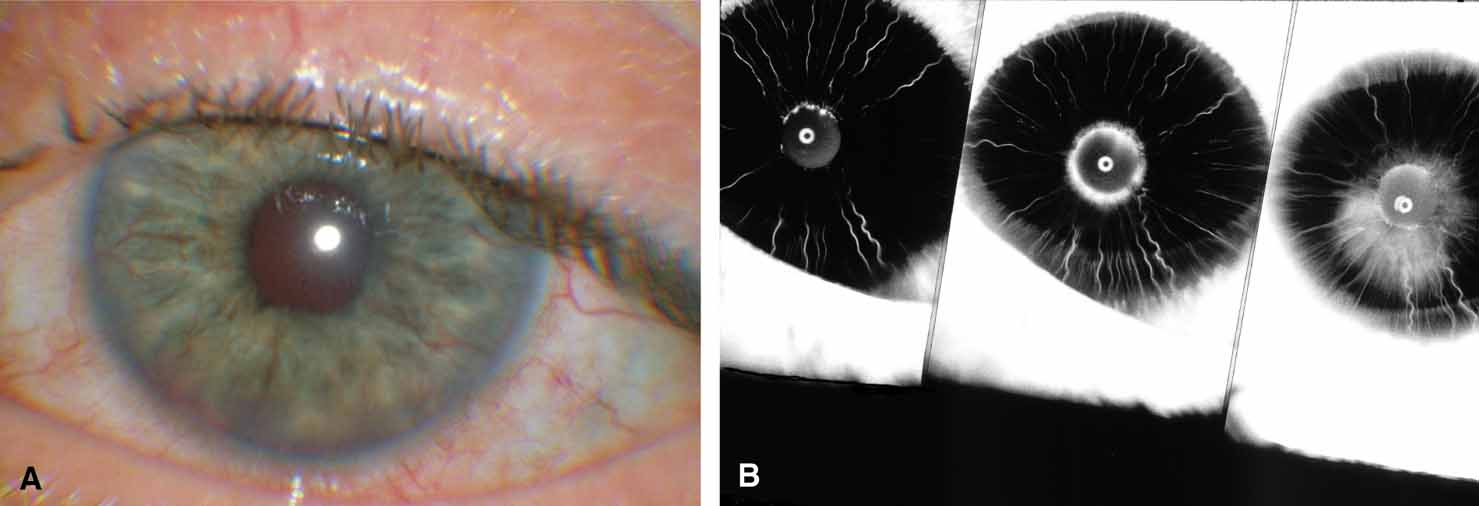

Active retinal involvement in acute toxoplasmosis may be associated with an acute elevation of intraocular pressure, sometimes producing corneal edema. When the cornea is cleared with topical glycerin, the angle is found to be open and a minimal anterior chamber reaction is present. The mechanism of the glaucoma is believed to be immune complex (antigen–antibody) deposition in the trabecular meshwork, rather than obstruction by cellular debris.21 The elevated pressure responds well to timolol or acetazolamide and does not require topical corticosteroids. Systemic treatment of the active retinitis should follow only if the optic nerve (positive Marcus Gunn), macular center, or peripapillary retina is involved. This unique entity will be missed if a fundus examination is not performed in all cases of hypertensive uveitis (Fig. 2).

The majority of cases of ghost cell glaucoma occur following vitrectomy for diabetic retinopathy, vitreous hemorrhage due to trauma, or vitreous hemorrhage following anterior segment surgery (i.e., cataract extraction or corneal transplant). Although studies suggest that a disruption of the anterior hyaloid face may be a necessary precedent, ghost cell glaucoma probably can occur with an intact hyaloid if a sufficient quantity of vitreous blood is present.27 The clinical presentation includes acute pressure elevation, corneal edema, and lack of keratic precipitates. Minute tan cells (ghost cells) may layer out, producing a pseudohypopyon or, if admixed with blood, a “candy-striped” hypopyon. (Fig. 3) Intraocular pressure elevations after diabetic vitrectomy raise concerns regarding concomitant neovascular glaucoma. However, neovascular glaucoma rarely develops in the immediate postvitrectomy period, unless some anterior segment neovascularization was present preoperatively. Late-onset pressure elevations (> 6 to 8 weeks out) in a postvitrectomized diabetic eye usually signal neovascular glaucoma.